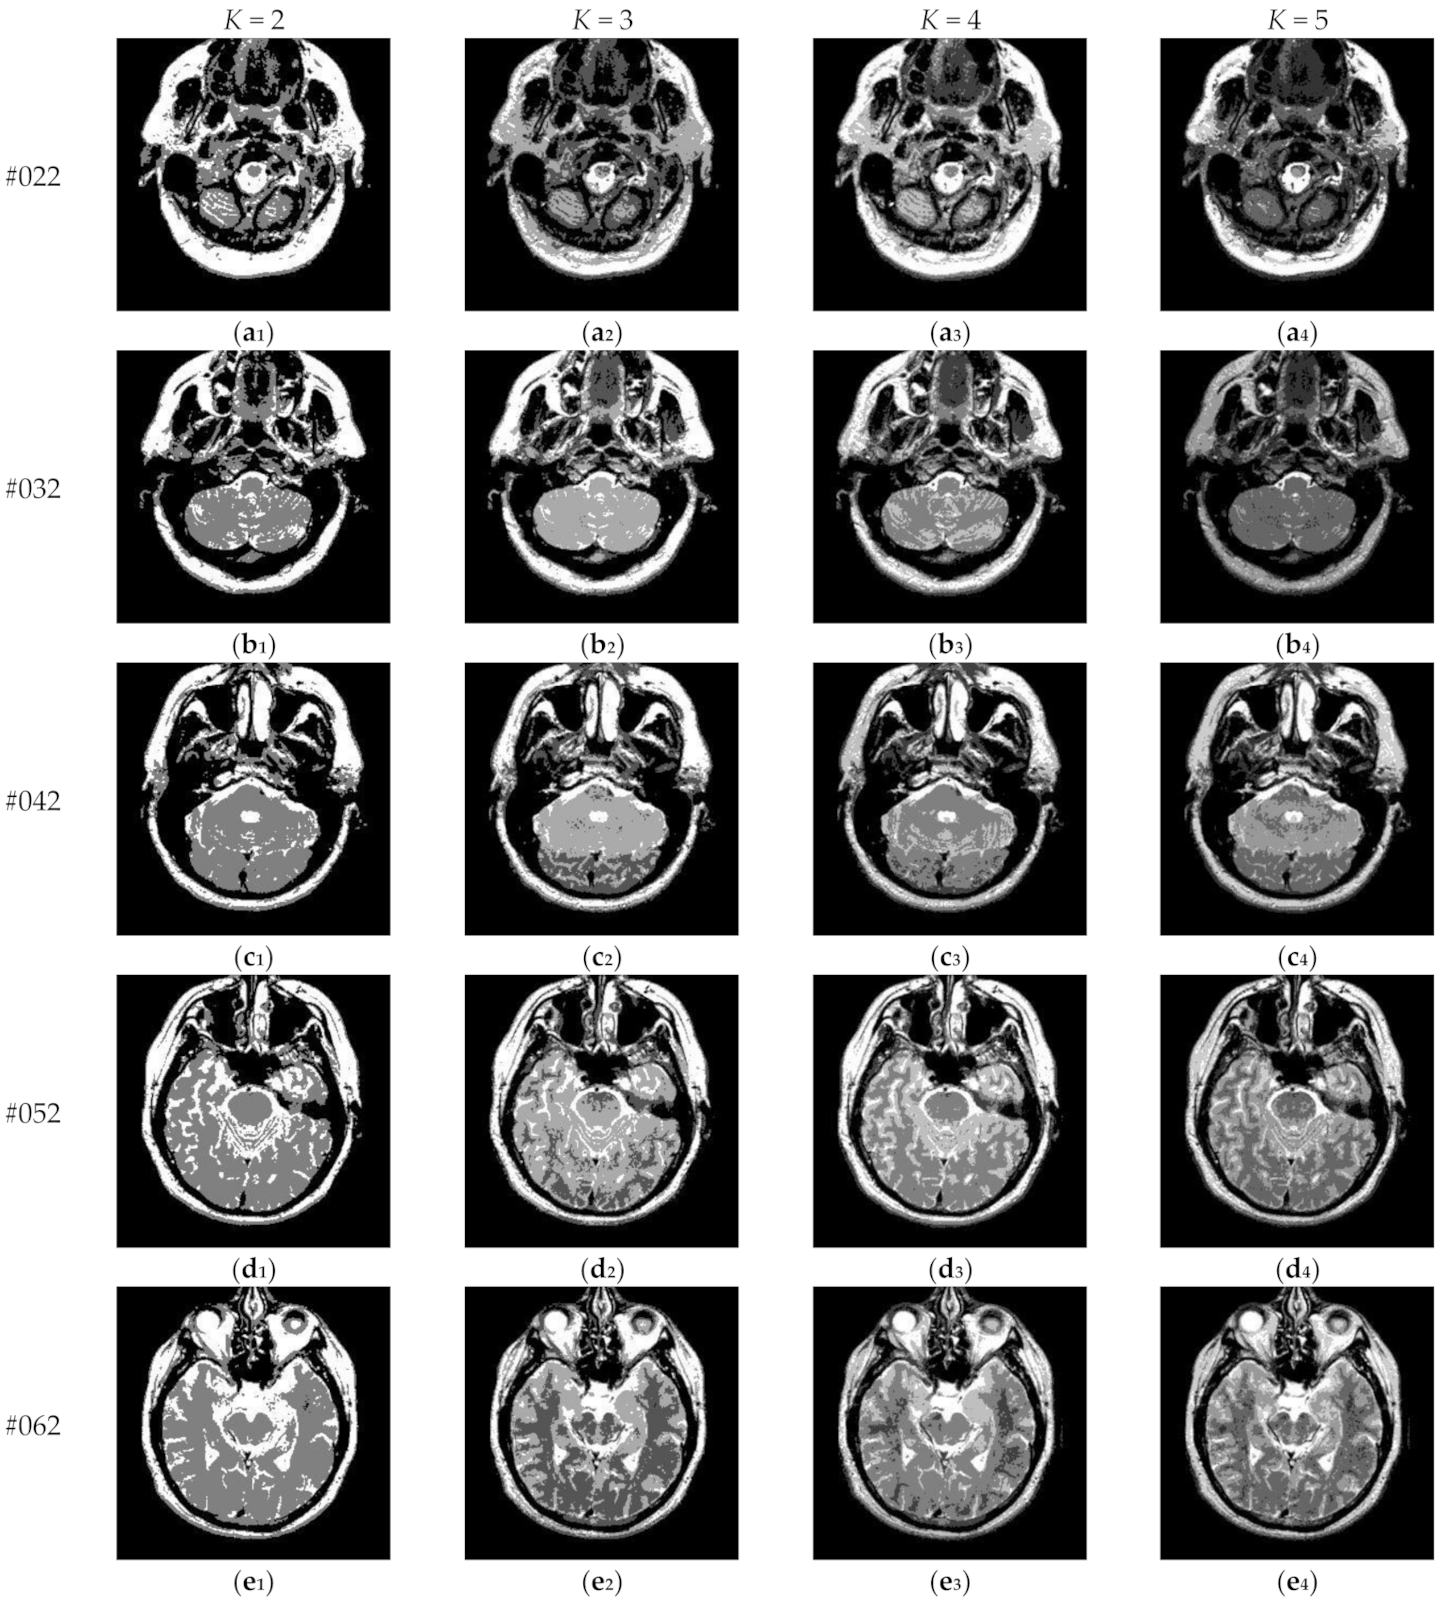

Figure 17 depicts the segmentation results of Proposed for brain slices #022~#112 with the number of thresholds K from 2 to 5. It can be seen that segmentation results with different threshold numbers have different effects. In general, the higher the level of thresholding, the better segmentation quality. Table 4 displays the comparison of optimal threshold values obtained by different algorithms with K = 2, 3, 4, 5. The proposed algorithm and LLF-DCE are based on the fusion scheme. The former combines two different segmentation results obtained by IIMT and HL-IIMT; the latter combines two different segmentation results obtained by LLF-Otsu and DCE-Otsu. In Table 4, it can be seen that the final thresholds selected by different algorithms are different from each other.

Figure 17.

Segmentation results obtained by the proposed algorithm for brain slices #022~#112: (a1–j1) display the results of 2-thresholding; (a2–j2) display the results of 3-thresholding; (a3–j3) display the results of 4-thresholding; (a4–j4) display the results of 5-thresholding.